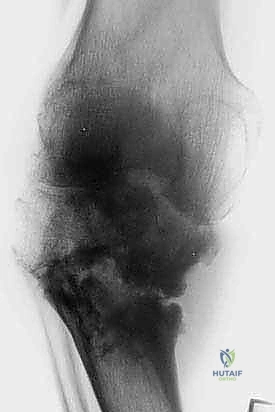

حتى الأورام الحميدة، مثل الورم ذو الخلايا العملاقة (Giant Cell Tumor) أو الأورام الغضروفية (Chondroblastoma)، يمكن أن تكون "عدوانية محلياً". هذا يعني أنها تنمو وتأكل العظم المحيط بها، مما يضعف الهيكل العظمي ويؤدي إلى كسور مرضية، ويهدد بانهيار المفصل القريب. هنا يكمن التحدي: كيف نزيل الورم بالكامل دون تدمير العظم السليم المتبقي؟

بناءً على التقييم الدقيق (الأشعة السينية، الرنين المغناطيسي، الخزعة)، يحدد الأستاذ الدكتور محمد هطيف الخطة العلاجية الأنسب، والتي تتدرج كالتالي: